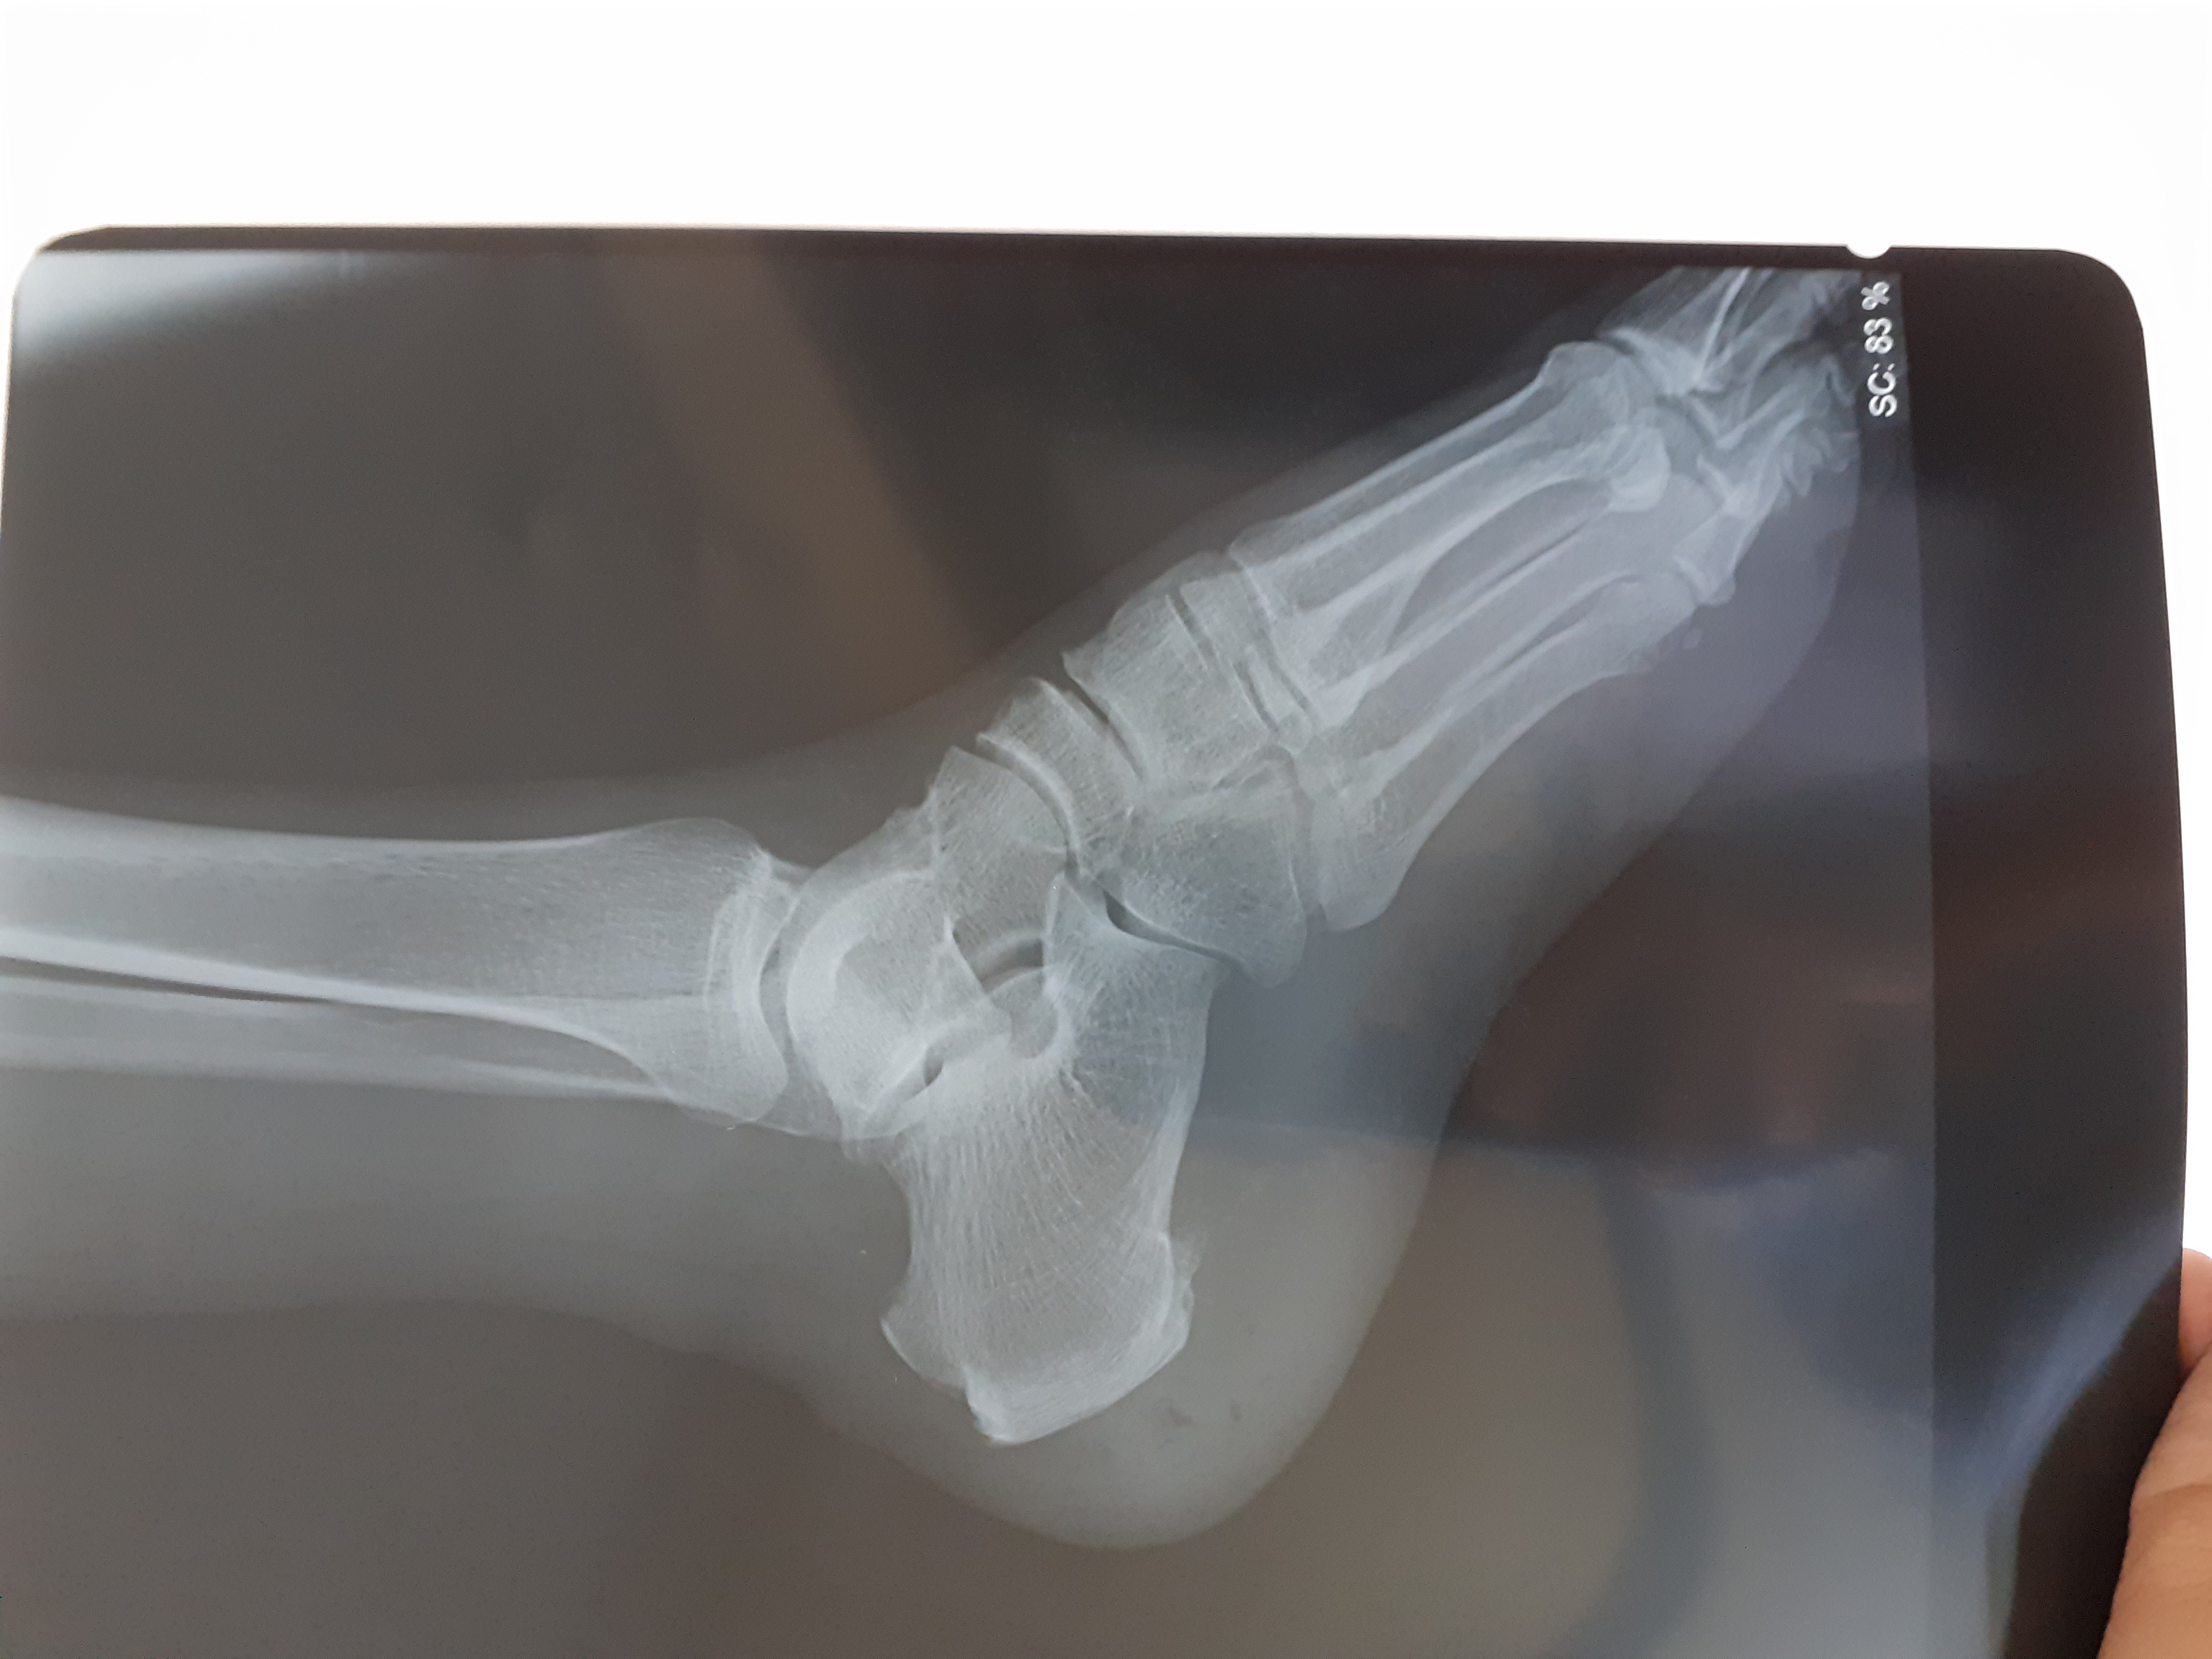

X-ray of diabetic foot